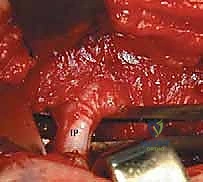

الخطوة 4: تحرير وتر العضلة الحرقفية القطنية (Psoas Tendon Release)

هذا هو أحد أهم أجزاء العملية. وتر العضلة الحرقفية القطنية يكون مشدوداً جداً في حالات DDH ويشكل حاجزاً يمنع رأس الفخذ من النزول إلى مكانه. يقوم الدكتور هطيف بعزل هذا الوتر وقطعه بدقة، مما يزيل الضغط الفوري عن المفصل.